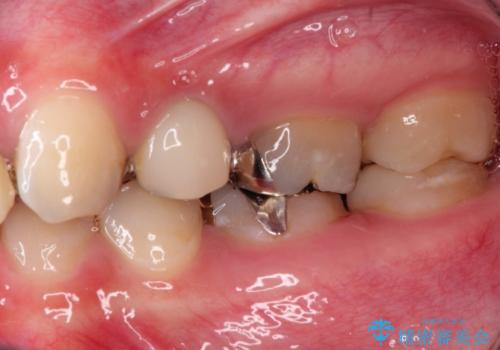

- 保険治療で装着されたかぶせ物と詰め物を変更したいとのことで来院されました。

自然なオールセラミックへ変更することとなりました。

金属を使わないセラミックへ変更することで、自然な見た目になるとともに、ぴったりとした精度の高いかぶせ物を装着することができました。